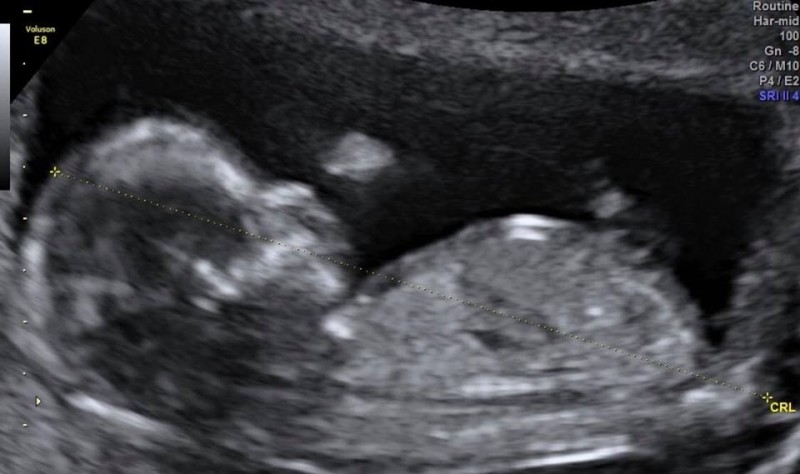

〔記者羅子欣/台北報導〕35歲「娃娃」魏如萱今凌晨、也是母親節當天,在臉書分享超音波照,宣布當媽了,目前已經懷孕3個月,她透露:「當我們沒有想太多的時候,這個美好的禮物悄悄的來了。」更幽默要粉絲猜猜看寶寶性別。她1個月前曾被爆進出婦產科,當時她以胖了為由否認,直到今天才認了懷孕,應是要遵循3個月不能說的傳統,而針對懷孕一事她經紀人回應,她和男友隆宸翰目前還沒有結婚,但「一切都在計畫中」,之後的演出也會照常舉行。